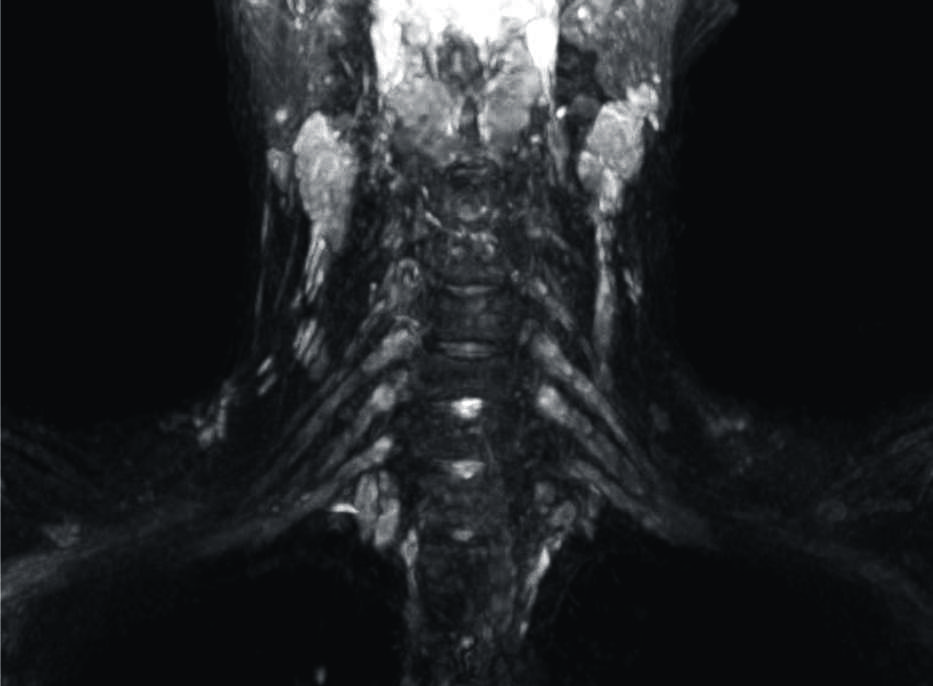

Figura 11

Sindrome de Parsonage Turner en un joven de 18 años.

Secuencia neurográfica IDEAL water en ponderación T2, en la que se observa engrosamiento e hiperseñal de los troncos y divisiones del plexo braquial izquierdo (flechas).